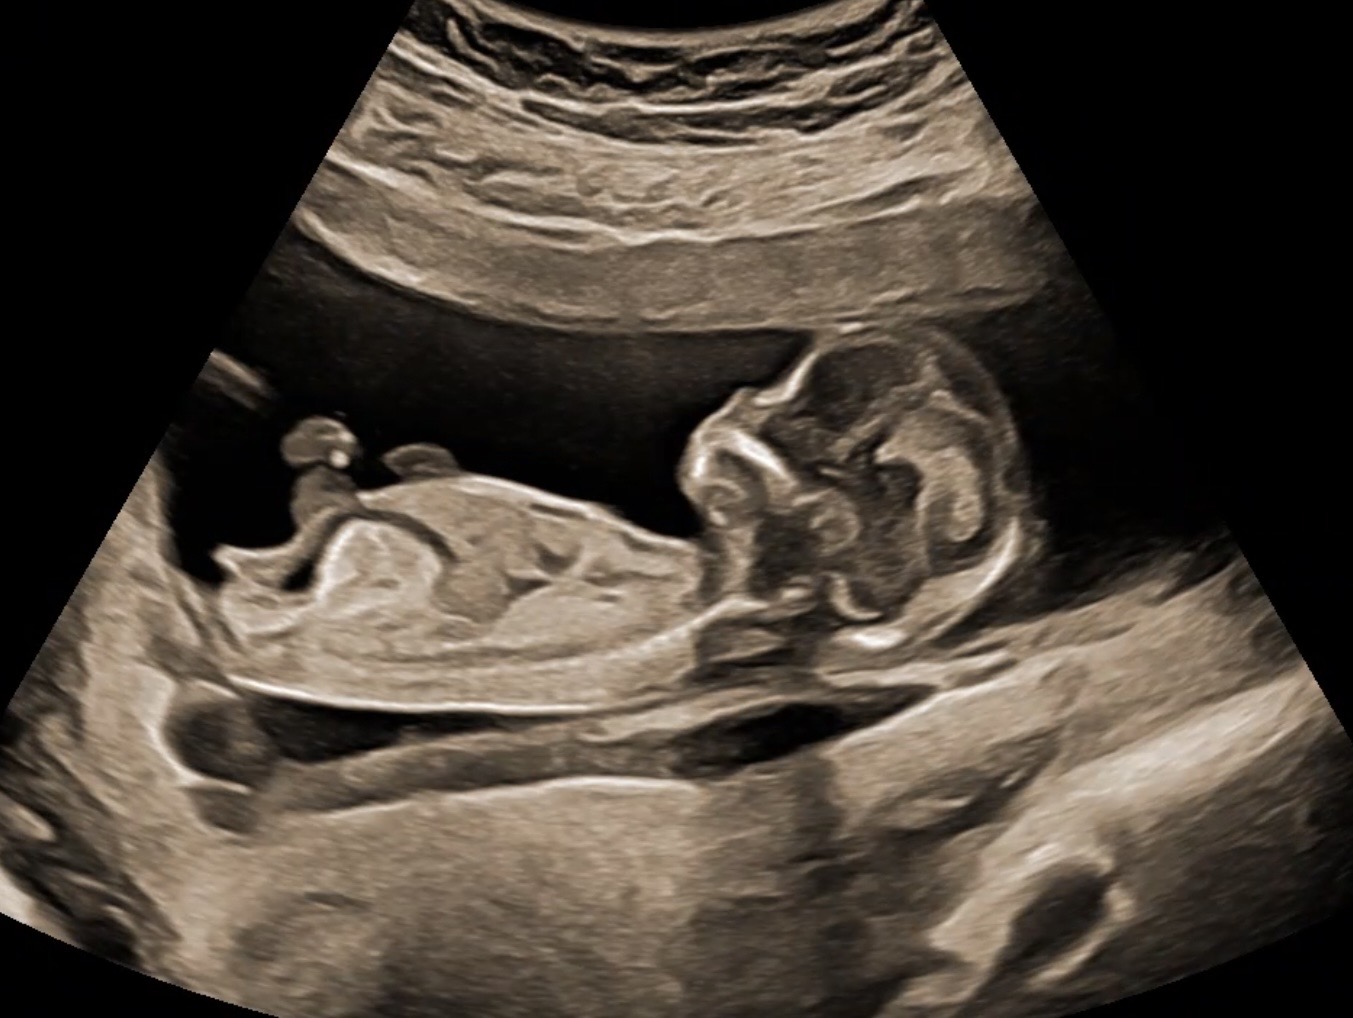

Hej dziewczyny...widzicie plec? Lekarka twierdzi, że 99% dziewczynka....? 12+4 z OM, 13+5 z USG.

IMG_6415.jpeg

• IMG_6429.jpeg

Nie jestem lekarzem, a skoro lekarz jest pewien na 99% to raczej ciężko o pomyłkę… chociaż wg tego zdjęcia wychodzi chłopak 😂 córka miała podobne zdjęcie do Twojego w 12tc, synkowi bardziej wystawał wyrostek do góry.